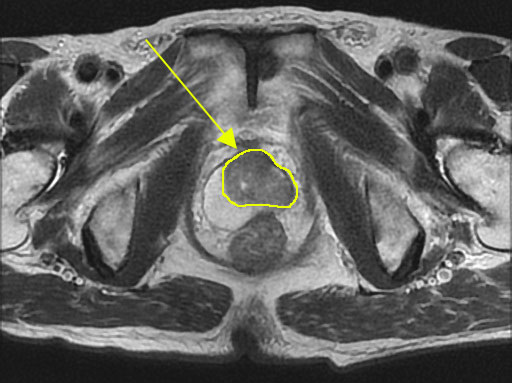

組織検査の結果、前立腺がんの診断がついたら、MRI、CT、骨シンチなどの画像検査によりがんの広がりや転移の有無を検査します。

前立腺がんMRI

※前立腺がんのMRI画像